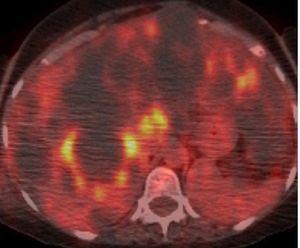

A pesar de que la EPQH es generalmente asintomática, algunos pacientes suelen experimentar complicaciones agudas o crónicas. Las complicaciones agudas más frecuentes de la EPQH incluyen infección y hemorragia intraquística. La infección quística suele presentarse con dolor localizado, fiebre, leucocitosis, velocidad de sedimentación elevada y, a menudo, fosfatasa alcalina elevada. Generalmente es monomicrobiana y causada por enterobacteriáceas. Una TC o una RM suelen diferenciar entre una infección o una hemorragia (figura 8 A y B). La tomografía por emisión de positrones con 18-fluorodesoxiglucosa (TEP-FDG) puede ser de gran utilidad en la identificación de quistes infectados en hígados poliquísticos (figura 9). Las complicaciones crónicas se deben generalmente a un agrandamiento masivo del hígado o a un efecto de masa debido a un quiste único dominante o a un grupo limitado de quistes. Los síntomas más frecuentes debidos al efecto de masa incluyen disnea, saciedad precoz, reflujo gastroesofágico y dolor lumbar mecánico. Otras complicaciones causadas por el efecto masa incluyen obstrucción del flujo eferente venoso hepático, compresión de la vena cava inferior, compresión de la vena porta o compresión del conducto biliar, que se manifiesta como ictericia obstructiva.

Figura 9. Imagen de tomografía por emisión de positrones con 18-fluorodesoxiglucosa (TEP-FDG) que demuestra una intensa captación circular de FDG en la pared de un quiste hepático, lo que sugiere una infección intraquística.